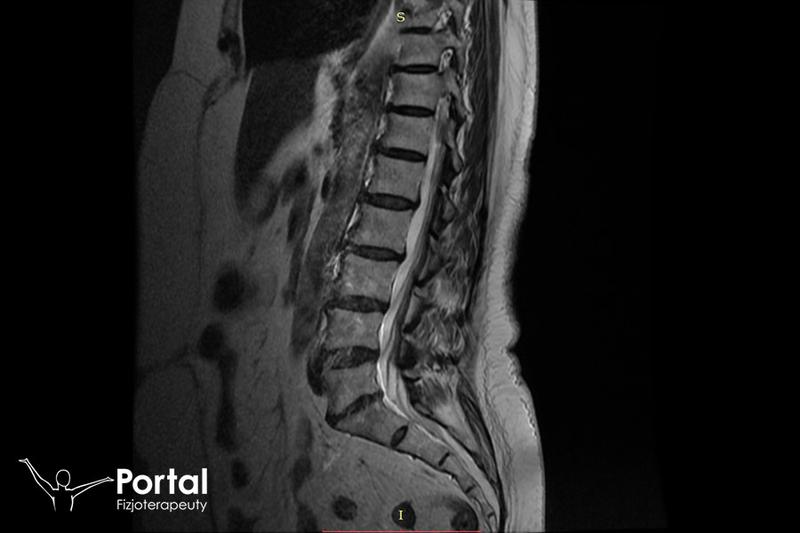

W okresie poporodowym ciało przechodzi liczne zmiany i regenerację, co często wiąże się z bólem w różnych miejscach, na przykład w dolnym odcinku kręgosłupa. Problem bólu kości ogonowej dotyka wiele młodych mam. W trakcie trudnych narodzin kość ogonowa może ulec urazowi, co w efekcie prowadzi do dyskomfortu podczas siedzenia oraz w codziennych obowiązkach. Właśnie w takich sytuacjach niezwykle pomocne okazują się ćwiczenia rehabilitacyjne!